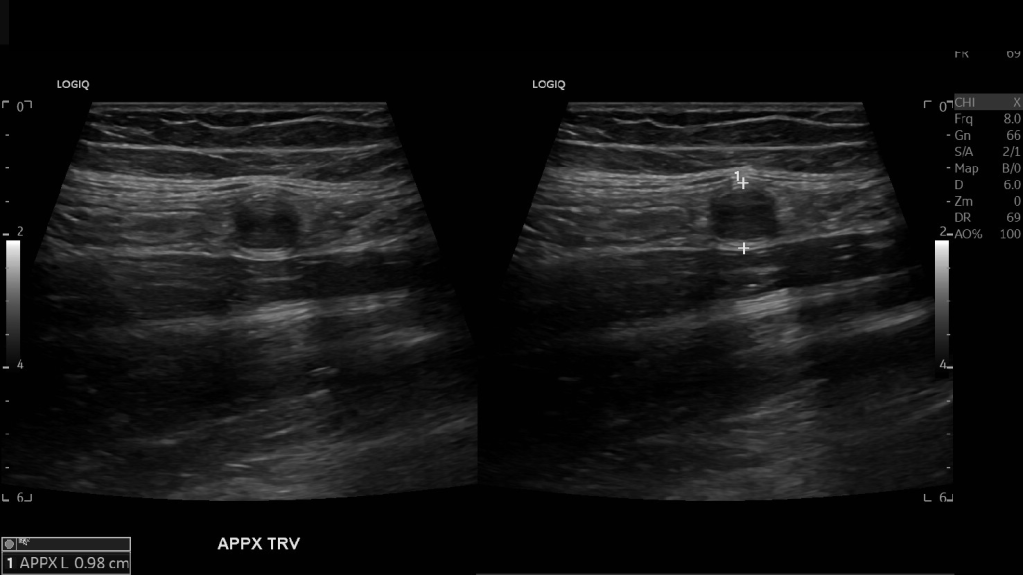

Appendicitis 12

0.9 cm positive appendicitis, with peripheral free fluid, and fat stranding.